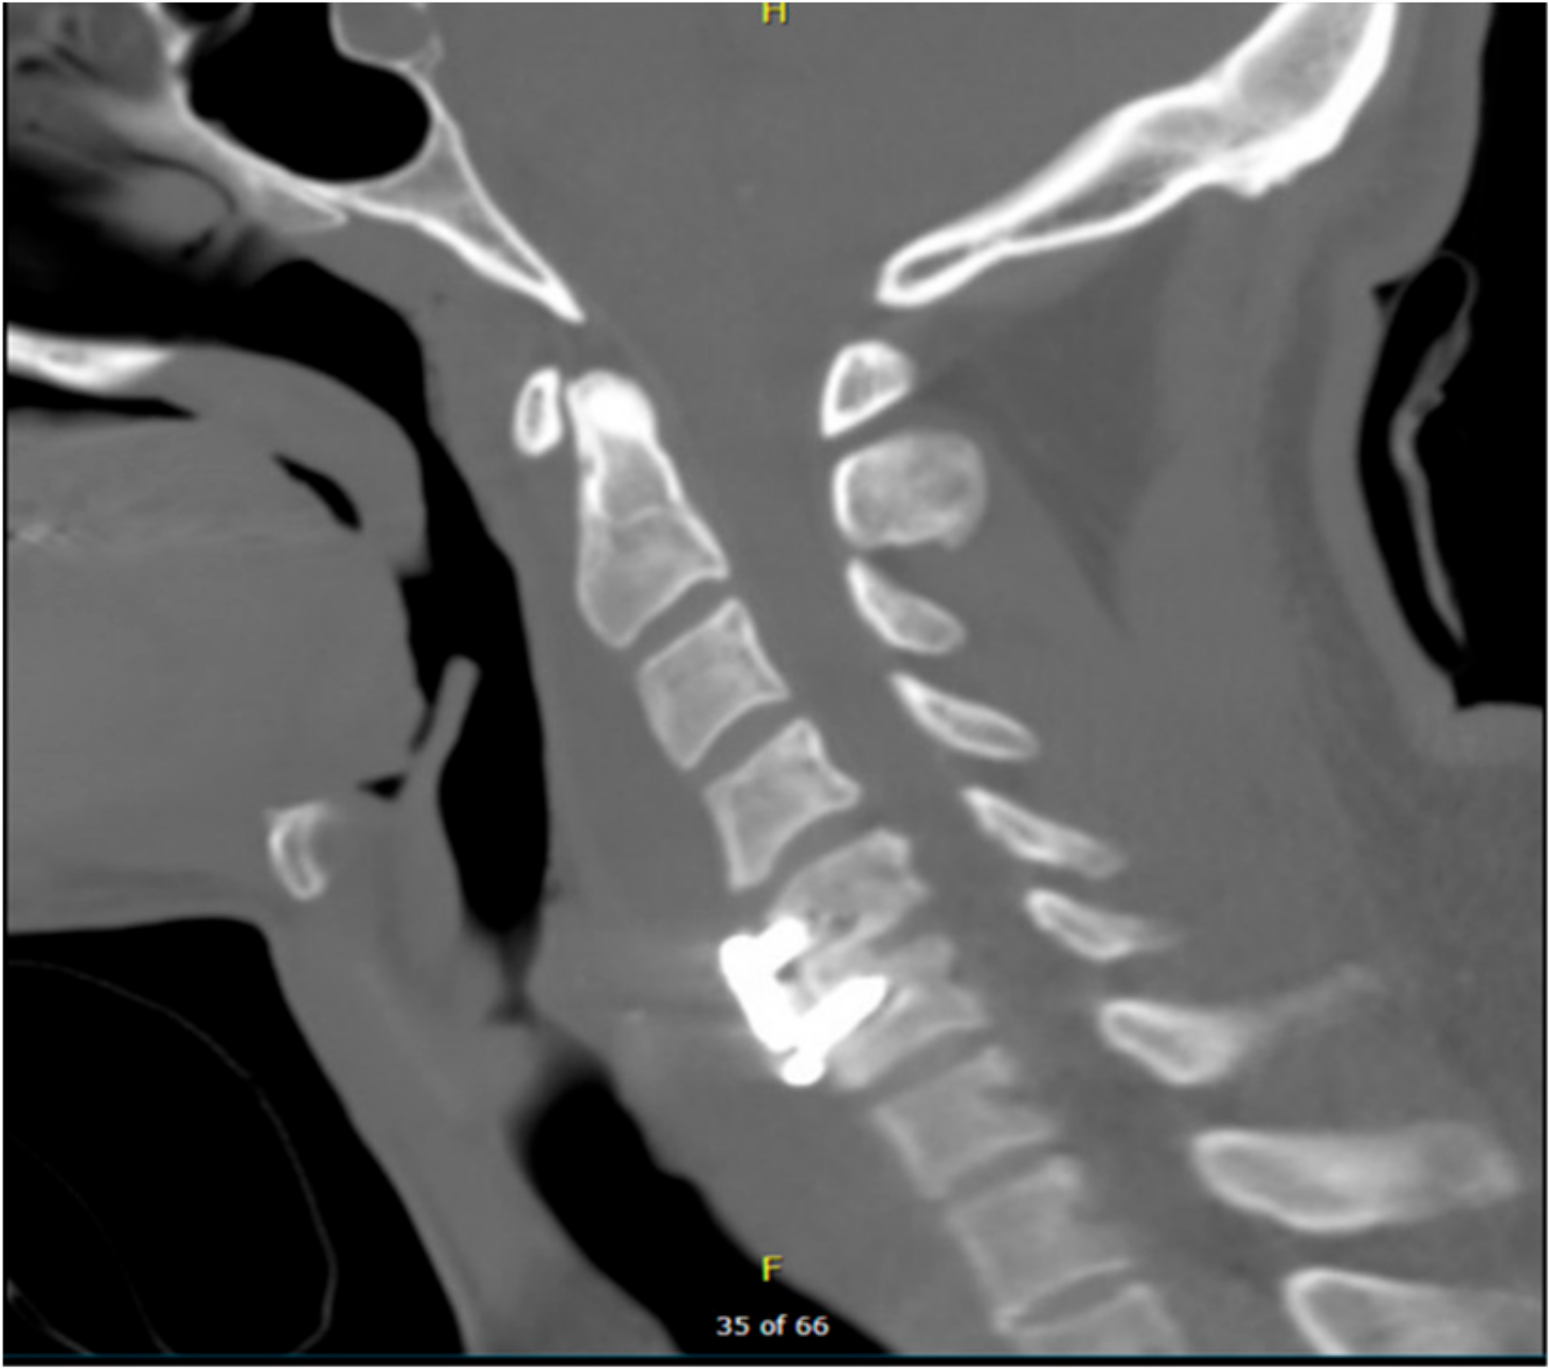

A postoperative CT scan confirmed the proper anterior fixation of the plate screws, interbody device, and bone graft placement following the patient’s discectomy and arthrodesis (Figure 2). Postoperative anterior and lateral X-rays (Figure 3b,a respectively) were also obtained in order to visualize and confirm proper placement of the anterior cervical plate and evaluation of alignment.

Figure 2. Postoperative CT scan showing spinal cord decompression following surgical discectomy and anterior arthrodesis of the C5–C6 vertebrae. CT scan = computerized tomography scan.